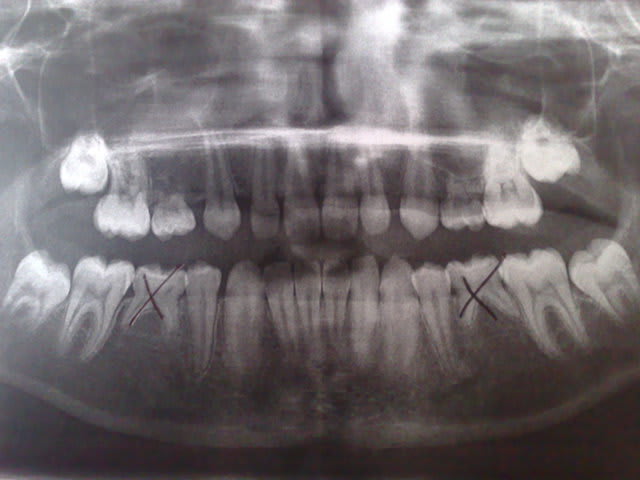

Pour ce patient de 12 ans en rétromandibulie. (Désolé pour la qualité de la photo)

L'ortho suggère extraction de 75/85 puis idem pour 55/65.

Puis pose d'implants (qu'il pose car stomato aussi accessoirement).

où sont passées 14/24?

@Arès: Les 14/24 étaient également en agénésie.

Le problème c'est le maintien de l'os surtout en bas car en haut y'a pas d'après ton otp.